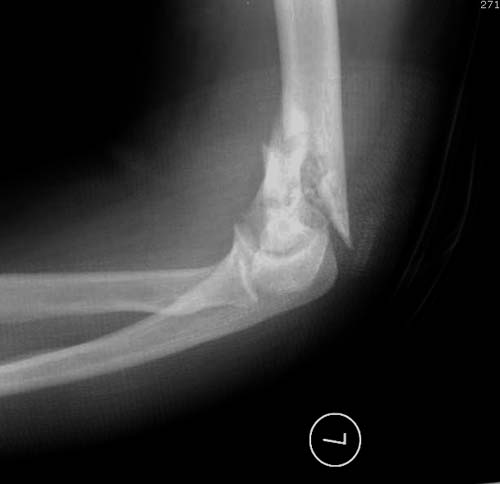

Re: Перелом дистального отдела плеча

Отсутствие фиксирующего материала минус, а наличие ЭОП повышает шансы сделать закрытую репозицию мыщелков. При наличии опыта можно аппаратом, но в нижней трети плеча имеется риск повреждения нервов.

Остеотомию локтевого отростка надо делать только тогда, когда нет возможности репонировать сустав закрыто, иначе много случаев несращений, когда фиксация проведена винтом, или когда не соблюдается технология методом Вебера. Более ожидаемый результат современными пластинами.